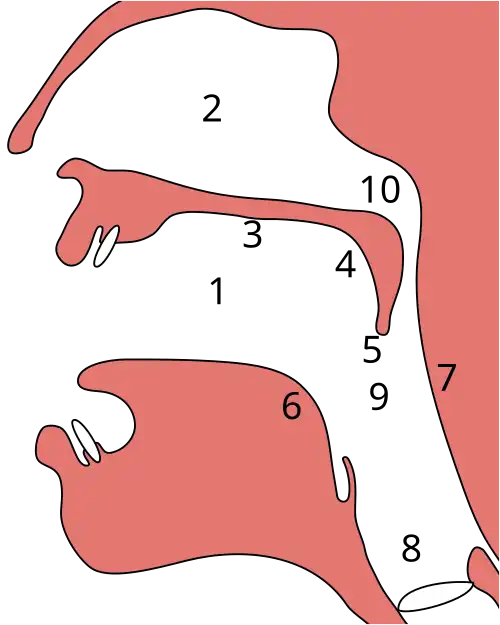

Velopharyngealer Verschluss

2 - Nasenhöhle (Cavum nasi)

3 - harter Gaumen (Palatum durum)

4 - weicher Gaumen (Palatum molle)

5 - Gaumenzäpfchen (Uvula)

6 - Zungenwurzel (Radix linguae)

7 - Rachenhinterwand

8 - Schlundrachen (Laryngopharynx oder Pars laryngea pharyngis)

9 - Mundrachen (Oropharynx oder Pars oralis pharyngis)

10 - Nasenrachen (Nasopharynx oder Pars nasalis pharyngis)

Der velopharyngeale Verschluss (VP-Verschluss; auch velopharyngealer Abschluss - VPA - oder nasopharyngealer Verschluss) ist der kurzzeitige physiologische Verschluss des Nasenrachens (lat. Nasopharynx) durch das Gaumensegel (lat. Velum palatinum; weicher Gaumen - lat. Palatum molle). Durch den velopharyngealen Verschluss wird der Nasopharynx gegenüber dem Oropharynx abgedichtet, während des Sprechens schließen die velopharyngealen Muskeln den Oro- und Nasopharynx - velopharyngealer Sphinkter. Er ist für das Schlucken oder die Aussprache bestimmter Verschlusslaute wichtig. Der velopharyngeale Verschluss trennt bei der Bildung nichtnasaler Laute den Oropharynx vom Nasopharynx.

Beim Schluckakt, in der pharyngealen Transportphase, verhindert der velopharyngeale Verschluss des Gaumensegels gegen die Rachenhinterwand den Übertritt des Nahrungsbreis in die oberen Luftwege. Während des velopharyngealen Verschlusses bildet sich durch die Kontraktion der Rachenhinterwand an dieser ein querverlaufender Wulst, der Passavantsche Wulst, der sich dem Gaumensegel entgegenstreckt und den Verschluss verbessert.